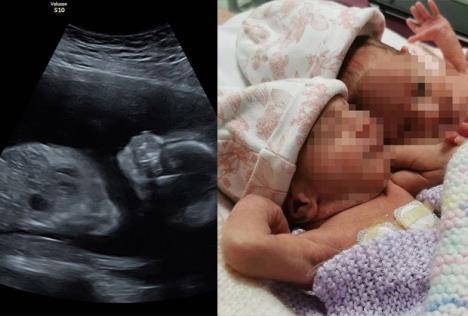

Bliznakinje je na svet donela surogat majka, a i na fotografijama sa ultrazvuka vidljivo je da su se i u njenom stomaku devojčice stalno grlile.

NA ULTRAZVUKU SE VIDELO NEŠTO NEOBIČNO! Sve vreme su bile zagrljene, a na porođaju je babica odmah uzela telefon da ih slika! Izvor: Instagram